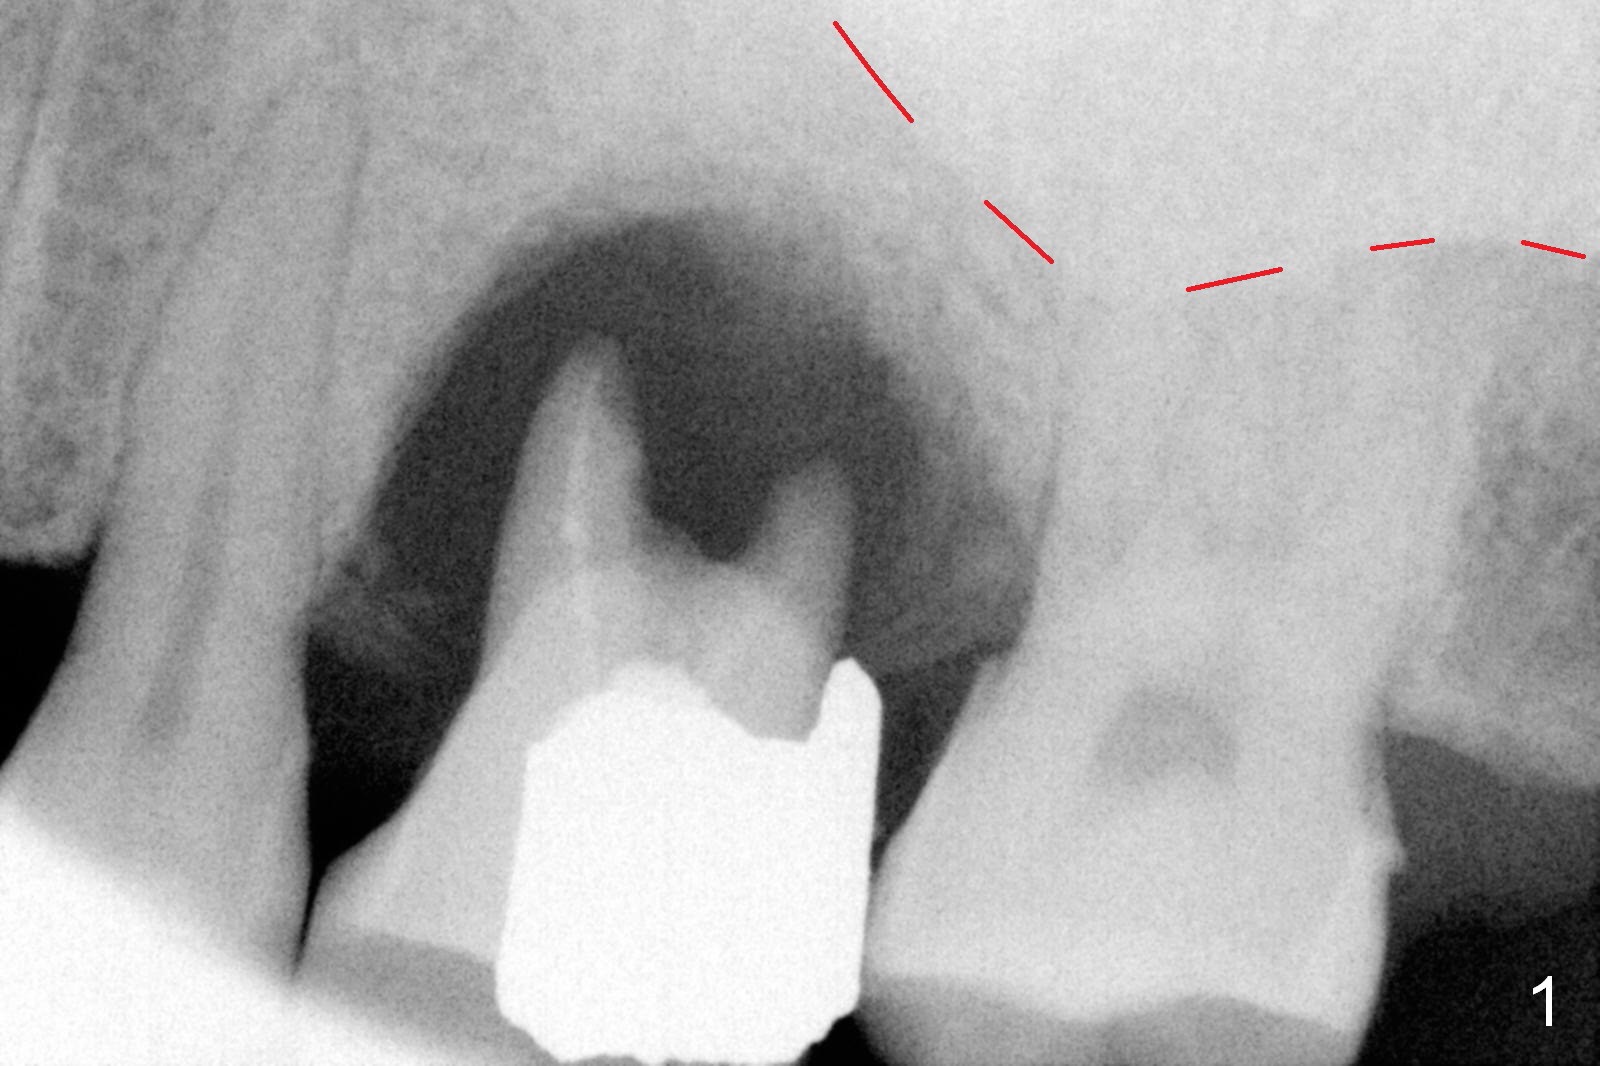

The tooth #14 of a 52-year-old lady had severe bone resorption 6 years ago (Fig.1 (red dashed line: sinus floor)). The bone resorption persists after the tooth exfoliated (Fig.2). Clinically, the buccal plate (Fig.4 (occlusal view) upper panel: B) is concave (take preop photos). #15 scalpel will be used for incision (red line in Fig.4 lower panel, near the lingual plate (L)) and initiation of bone expansion. The latter is followed by bone scalpels, bone blades and RTs at the depth of 14 mm. A 4.5x17 mm Tatum tapered tap is used for 14 mm. PA is taken. If the bone is dense, the depth is less than 14 mm in bone. Use RT2,3 to reach 17 mm. A 5x14 mm bone-level implant is placed (Fig.3). Crown cementation will be done for the tooth #3 before surgery.